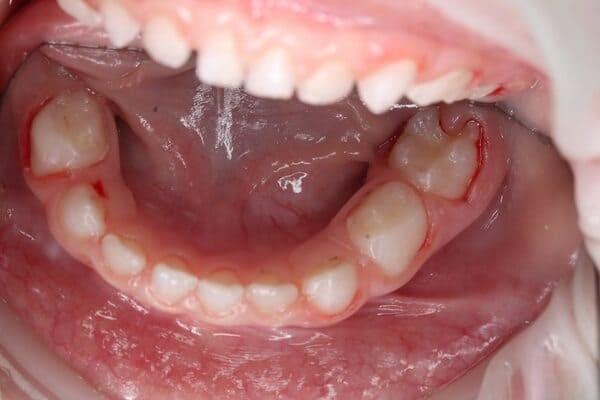

Дівчинка 4,5 років скаржилась на біль в нижньому зубі справа. В зв’язку з високою складністю процедур і значним об’ємом лікування (8 зубів) та після невдалої спроби лікування в звичайному режимі було прийнято рішення про лікування в умовах анестезіологічного забезпечення. Видаленно запалену пульпу (“нерв”) та проведено лікування каналів нижнього зуба ліворуч, цей та сусідні зуби покриті металевими коронками через значний об’єм ураження. Проліковані всі зуби, які потребували допомоги, щоб в майбутньому уникнути болю, дискомфорту та поширення інфекції. Через три години лікування дівчинка може комфортно жувати і не відчувати болю і дискомфорту.